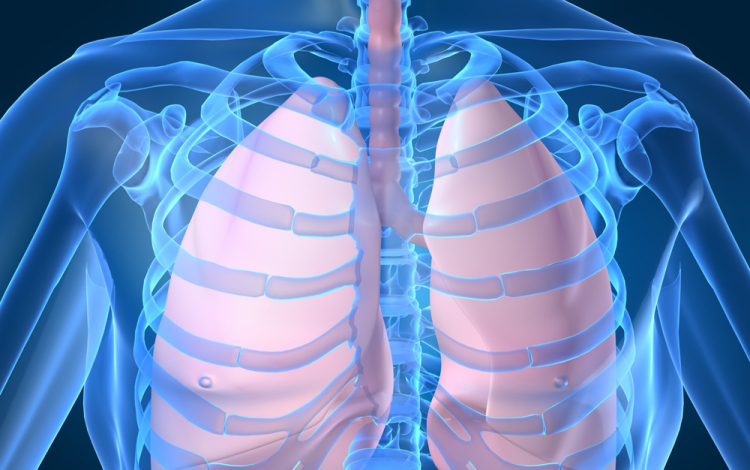

Húszan várnak tüdőátültetésre Magyarországon

Húszan várnak tüdő-transzplantációra az országban, tavaly 12 magyar betegen hajtottak végre ilyen szervátültetést külföldön

- mondta Kásler Miklós, az Országos Onkológiai Intézet főigazgatója vasárnap az M1 aktuális csatorna esti műsorában. A főigazgató ezt azzal kapcsolatban közölte, hogy még idén elvégezhetik az első tüdőátültetést Magyarországon.

Magyarországról tavaly 37 tüdőt szállítottak Bécsbe átültetési céllal; ha nálunk is elérhetővé válik a műtét, akkor várhatóan a környező országokból is Budapestre érkezik majd a betegek egy része Bécs helyett - mondta a főigazgató.